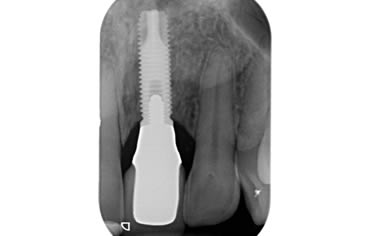

Missing upper front tooth replaced by dental implant and crown